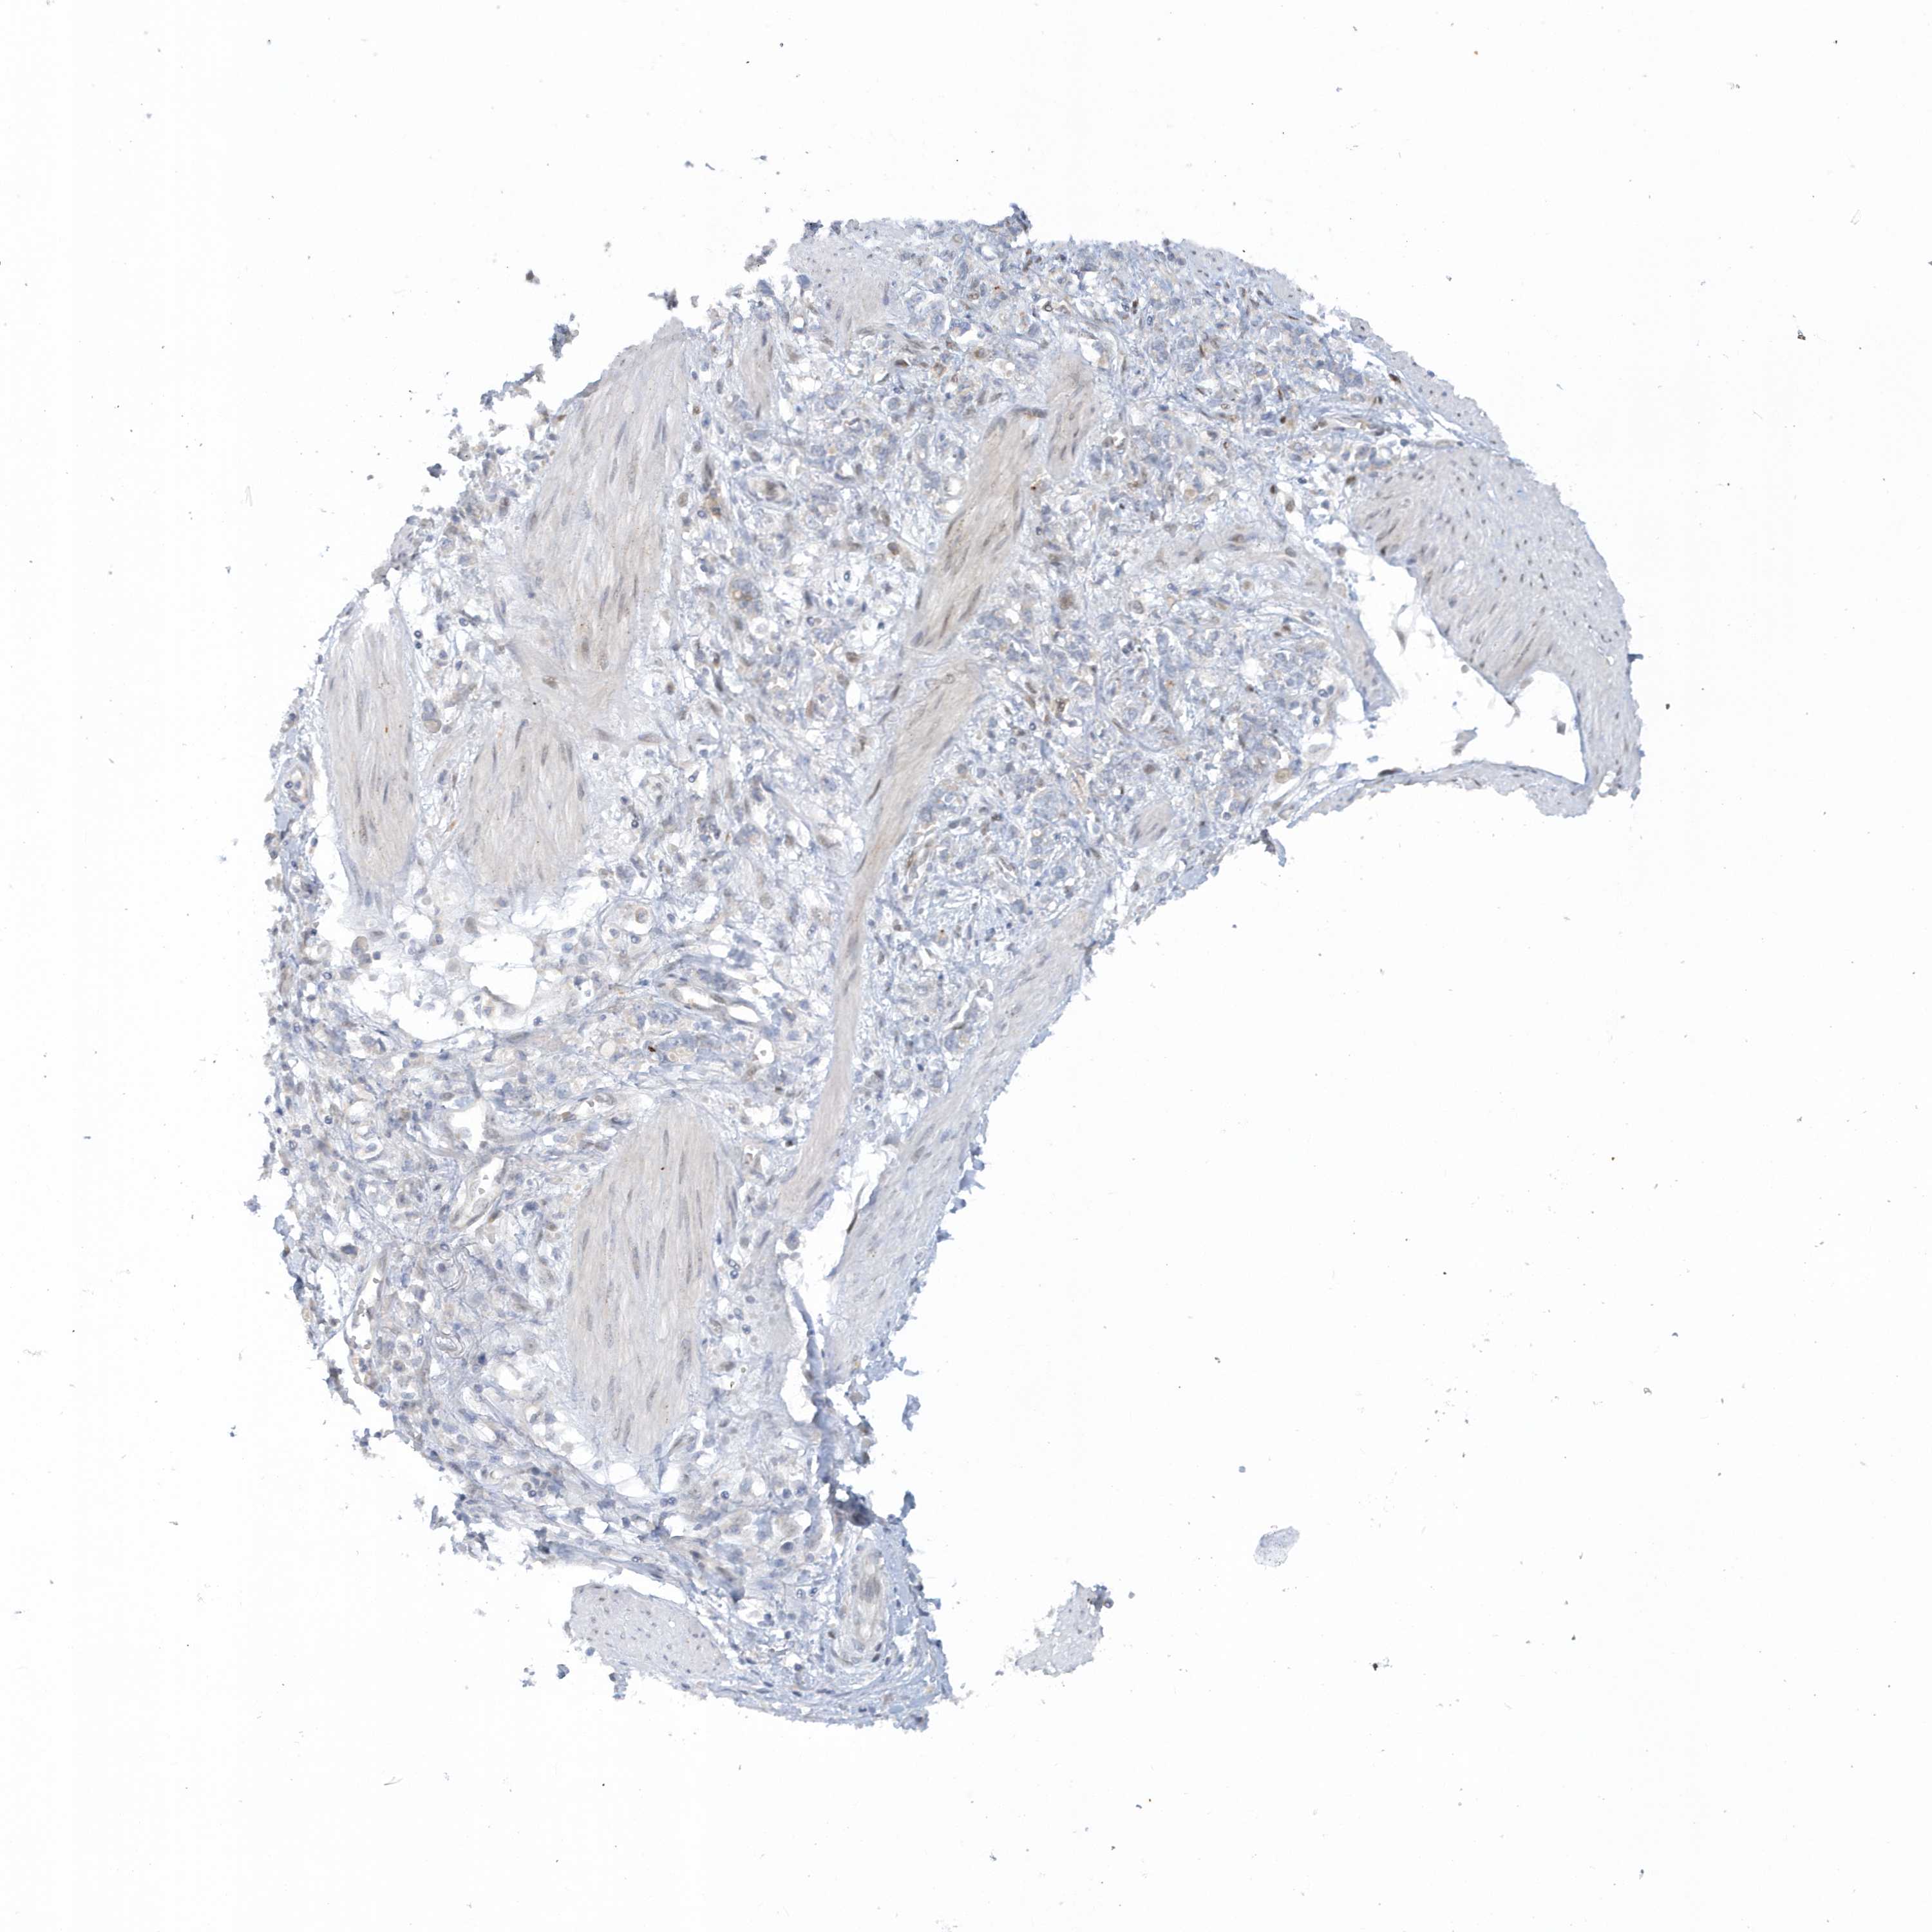

STOMACH CANCER - Protein expressioni

A mouse-over function shows sample information and annotation data. Click on an image to view it in a full screen mode. Samples can be filtered based on level of antibody staining by selecting one or several of the following categories: high, medium, low and not detected. The assay and annotation is described here.

Antibody stainingi

Antibody staining in the annotated cell types in the current human tissue is reported as not detected, low, medium, or high, based on conventional immunohistochemistry profiling in selected tissues. This score is based on the combination of the staining intensity and fraction of stained cells.

Each image is clickable and will lead to virtual microscopy that enables deeper exploration of all samples and also displays staining intensity scores, fraction scores and subcellular localization as well as patient and tissue information for each sample.

Antibody HPA036374

Staining

High

Medium

Low

Not detected

Intensity

Strong

Moderate

Weak

Negative

Quantity

>75%

75%-25%

<25%

None

Location

Nuclear

Cytoplasmic/membranous

Cytoplasmic/membranous,nuclear

Adenocarcinoma, NOS